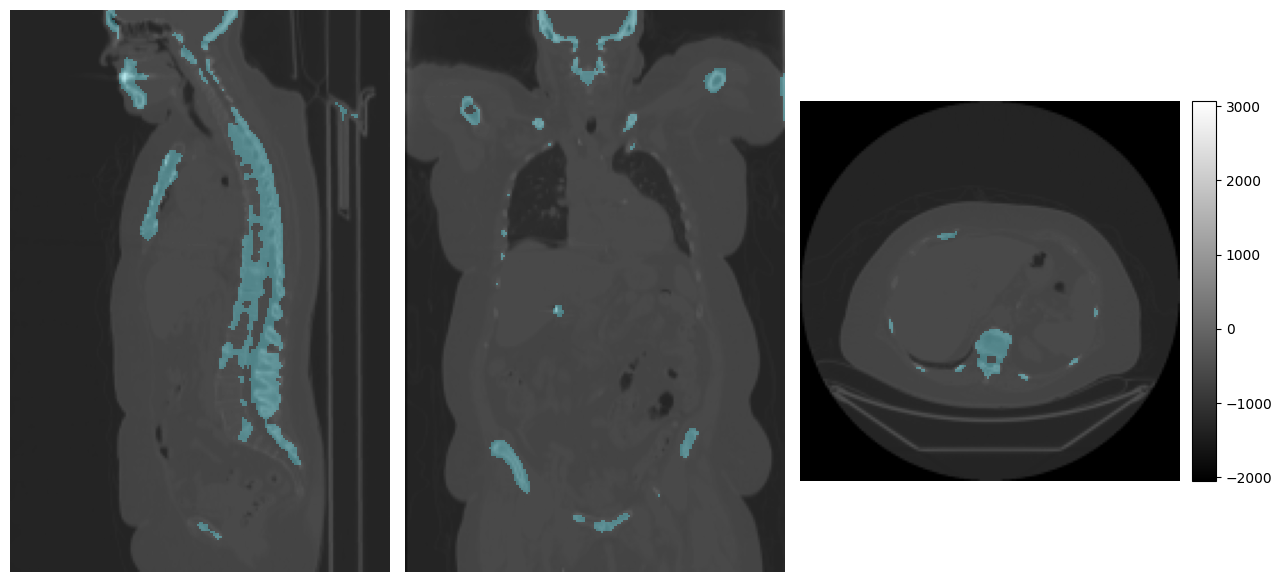

# Visualize the ground truth

print("Target:")

mpr_plot(ct_image[0], labels=bones_segmentation[0])

Target:

../../_images/tutorials_imfusion-sdk_4_model_inference_7_1.png